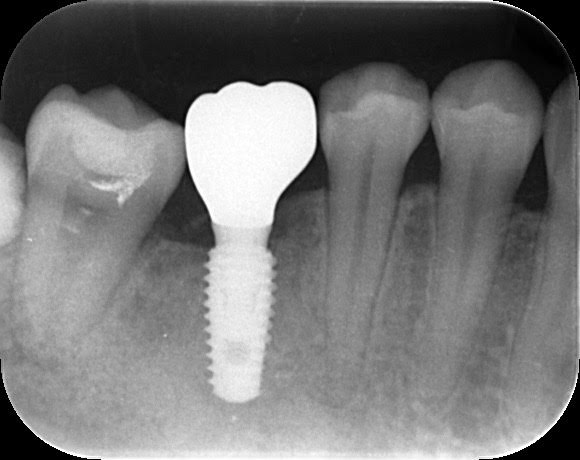

- 治療例 3

左下の奥歯を失った患者様の初診時口腔内写真です。

十分な骨量と歯茎があるケースでしたので、「切らない縫わないインプラント治療」を行うことになりました。

直径4.5ミリ長さ8ミリのインプラントを埋め込みました。

理想的な位置にインプラントが埋め込まれていることが、分かって頂けると思います。